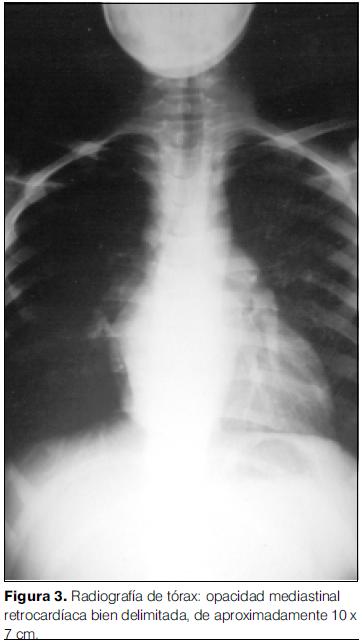

- Radiografía de tórax: opacidad mediastinal retrocardíaca densa de contornos lisos que impresiona levantar el bronquio fuente izquierdo. No hay lesiones focales pulmonares. Índice cardiotorácico aumentado para la edad (figura 3).